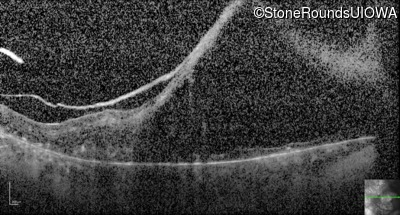

Optical Coherence Tomography - Right - 20/125 -2 sc

Exemplar / OCT Stack